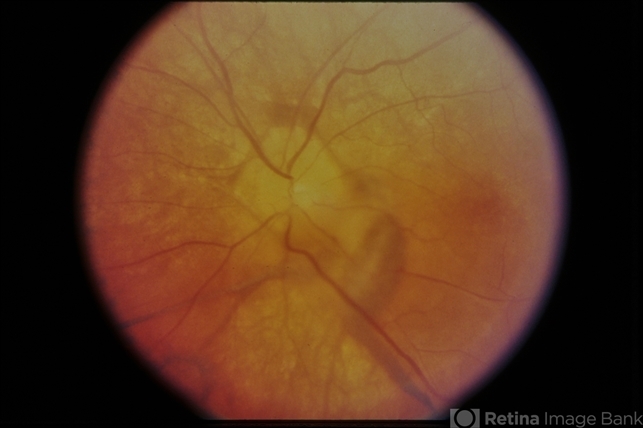

- VogtKoyanagiHarada

- Vogt-Koyanagi-Harada

- Vogt-Koyanagi-Harada, 35-year-old-female.